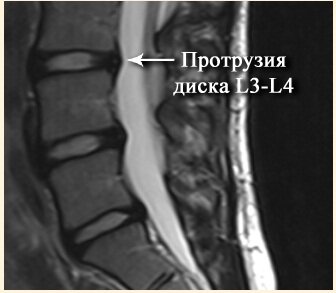

Как говорилось в начале статьи, чаще всего электрофорез применяют для лечения протрузии или грыжи межпозвоночного диска. Если по простому - это как "шишка" на колесе автомобиля, только в позвоночнике. Как это выглядит смотрите на картинках: